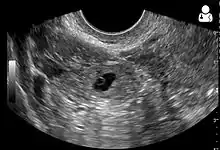

An ultrasound showing a gestational sac with fetal heart in the fallopian tube has a very high specificity of ectopic pregnancy. It involves a long, thin transducer, covered with the conducting gel and a plastic/latex sheath and inserted into the vagina.[32] Transvaginal ultrasonography has a sensitivity of at least 90% for ectopic pregnancy.[5] The diagnostic ultrasonographic finding in ectopic pregnancy is an adnexal mass that moves separately from the ovary. In around 60% of cases, it is an inhomogeneous or a noncystic adnexal mass sometimes known as the "blob sign". It is generally spherical, but a more tubular appearance may be seen in case of hematosalpinx. This sign has been estimated to have a sensitivity of 84% and specificity of 99% in diagnosing ectopic pregnancy.[5] In the study estimating these values, the blob sign had a positive predictive value of 96% and a negative predictive value of 95%.[5] The visualization of an empty extrauterine gestational sac is sometimes known as the "bagel sign", and is present in around 20% of cases.[5] In another 20% of cases, there is visualization of a gestational sac containing a yolk sac or an embryo.[5] Ectopic pregnancies where there is visualization of cardiac activity are sometimes termed "viable ectopic".[5]

Transvaginal ultrasonography of an ectopic pregnancy, showing the field of view in the following image